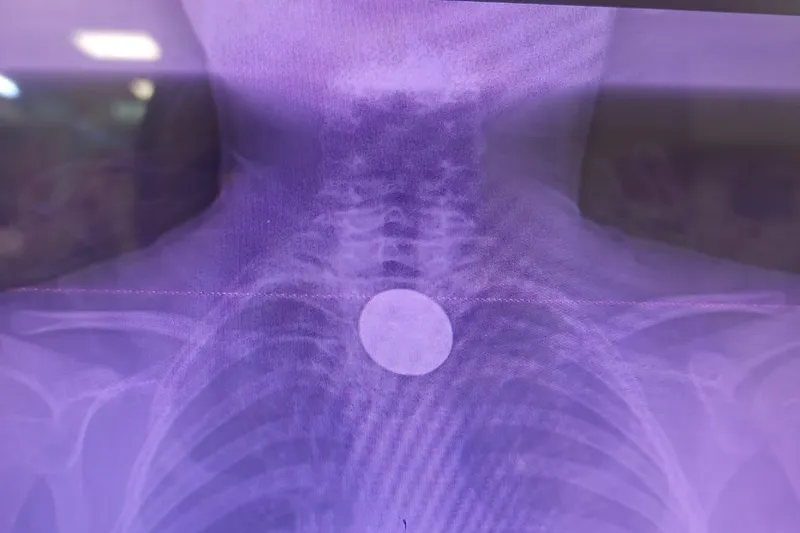

Yapılan incelemelerde 5 TL’lik madeni paranın Y.K.’nin yemek borusuna kadar ilerlediği belirlendi. Çocuk hastalarda ciddi solunum ve sindirim sistemi riskleri oluşturabilen bu durum üzerine ilgili branşlar vakit kaybetmeden harekete geçti.

Madeni paranın çıkarılması için Gastroenteroloji Uzmanı Dr. Yaren Dirik ile Kulak Burun Boğaz (KBB) Hekimi Dr. Yasin Gökçınar tarafından ortak bir girişim gerçekleştirildi. Alanında uzman ekiplerin koordineli çalışmasıyla madeni para herhangi bir komplikasyona yol açmadan başarıyla çıkarıldı.

“Hastanemize başvuran 8 yaşındaki hastamızın yemek borusuna kaçan madeni para, gastroenteroloji ve KBB ekiplerimizin koordineli çalışmasıyla başarılı bir şekilde çıkarılmıştır. Operasyon süreci sorunsuz geçmiş olup hastamızın genel durumu iyidir.”